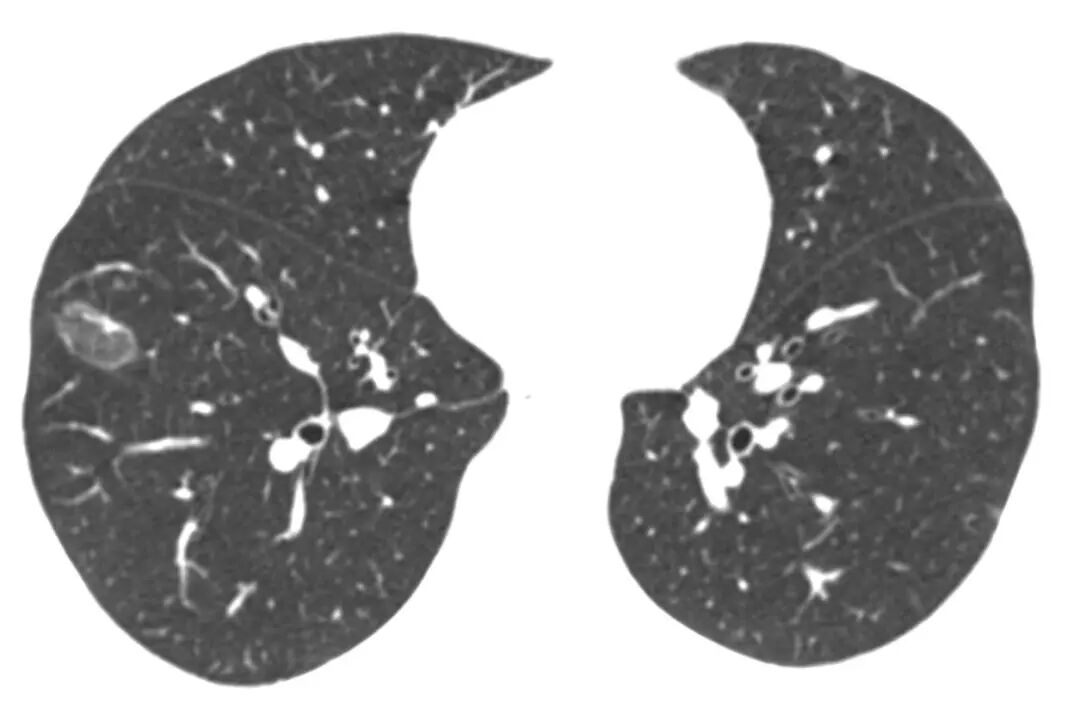

女性,59岁,粟粒性肺结核的基础上,双肺弥漫微结节伴反晕征。[2]

病例3:

男性,36岁,肺结核。反晕征由微小结节构成。[2]

病例6:

女性,38岁,肺结核。左肺上叶反晕征,外壁有结节。[2]

病例4:

35岁男性肺结核患者,发热、咳嗽、纳差2月,体重下降8kg,双肺少量爆裂音。肺CT:左胸膜增厚,左胸廓塌陷,右下肺可见反晕征。仔细看反晕征的外壁和中间都有很多微结节。[1]

病例2:

以上主要对比了肺结核与机化性肺炎的反晕征。机化性肺炎的反晕征相对质地均匀光滑,无结节。肺结核的反晕征则比较粗糙不均,仔细看其实是由无数个小点(微结节)「拼凑」成的,这与结核作为肉芽肿的病理特征也是相符合的。

肺结核导致的反晕征的特点是:反晕征的外壁以及内部有微小结节。我们来看一下不同疾病导致的反晕征的影像资料。